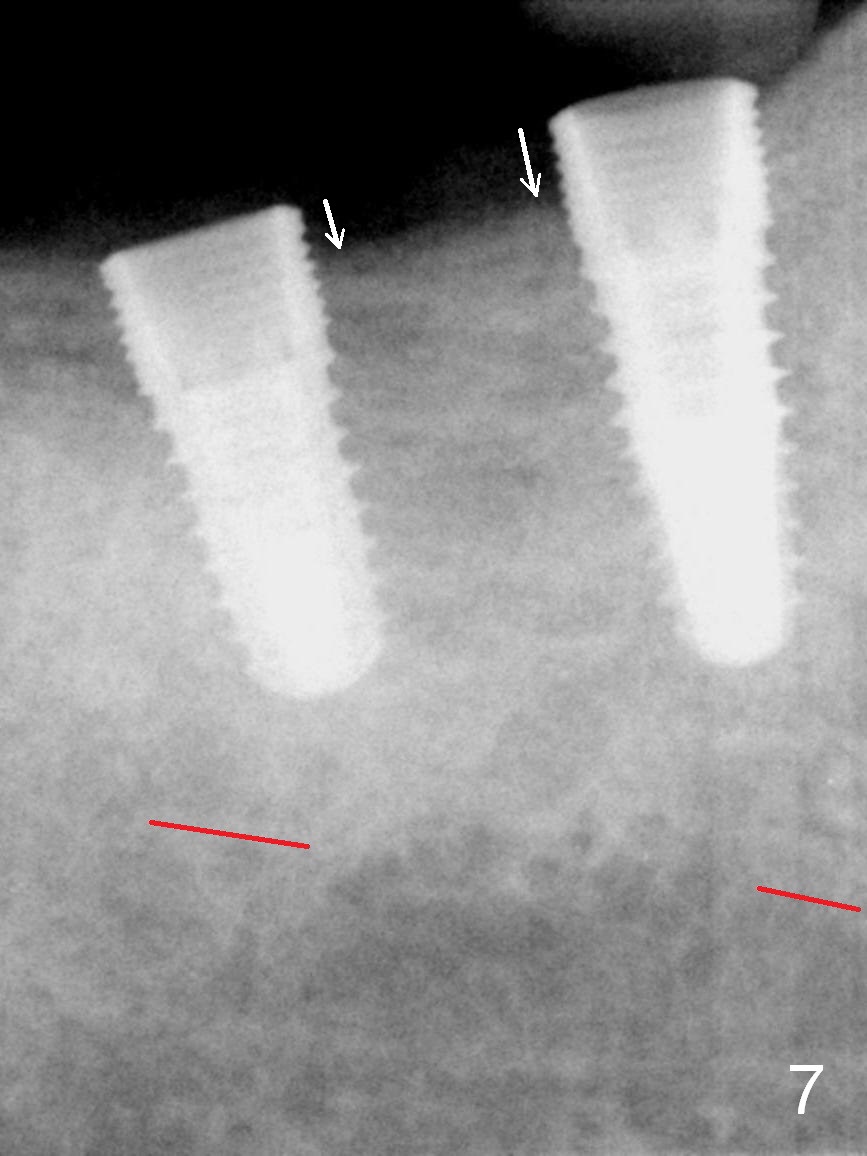

One month later, the patient returns for #30 and 31 implant placement. As planned, the initial depth is 10 and 8 mm (Fig.6). What is unexpected is deficiency in ridge width. Narrower implants (as compared to those on the left) are placed (Fig.7: 4.5x12 and 4.5x10 mm). With shorter implants, the implants are later placed deeper (as shown by arrows in Fig.7) so that almost all of the microthreads are buried in the bone. It is expected that there is less chance of thread exposure postop. The later turns out to be true 3.5 months postop (Fig.8 with 6.8x5(3) mm abutments). It appears that the abutment margin is supragingival (white dashed line: gingival margin) and should be trimmed prior to impression. Or change the abutments to ones with shorter cuff. It may be so for those at #18 and 19 (Fig.9: 4 months postop). Custom full arch trays will be used for impression with bite registration. In fact the mesial margin of #19 abutment is ~ 2 mm subgingival. A longer-cuff abutment is used (6.8x5(3) mm) at #19 before impression.